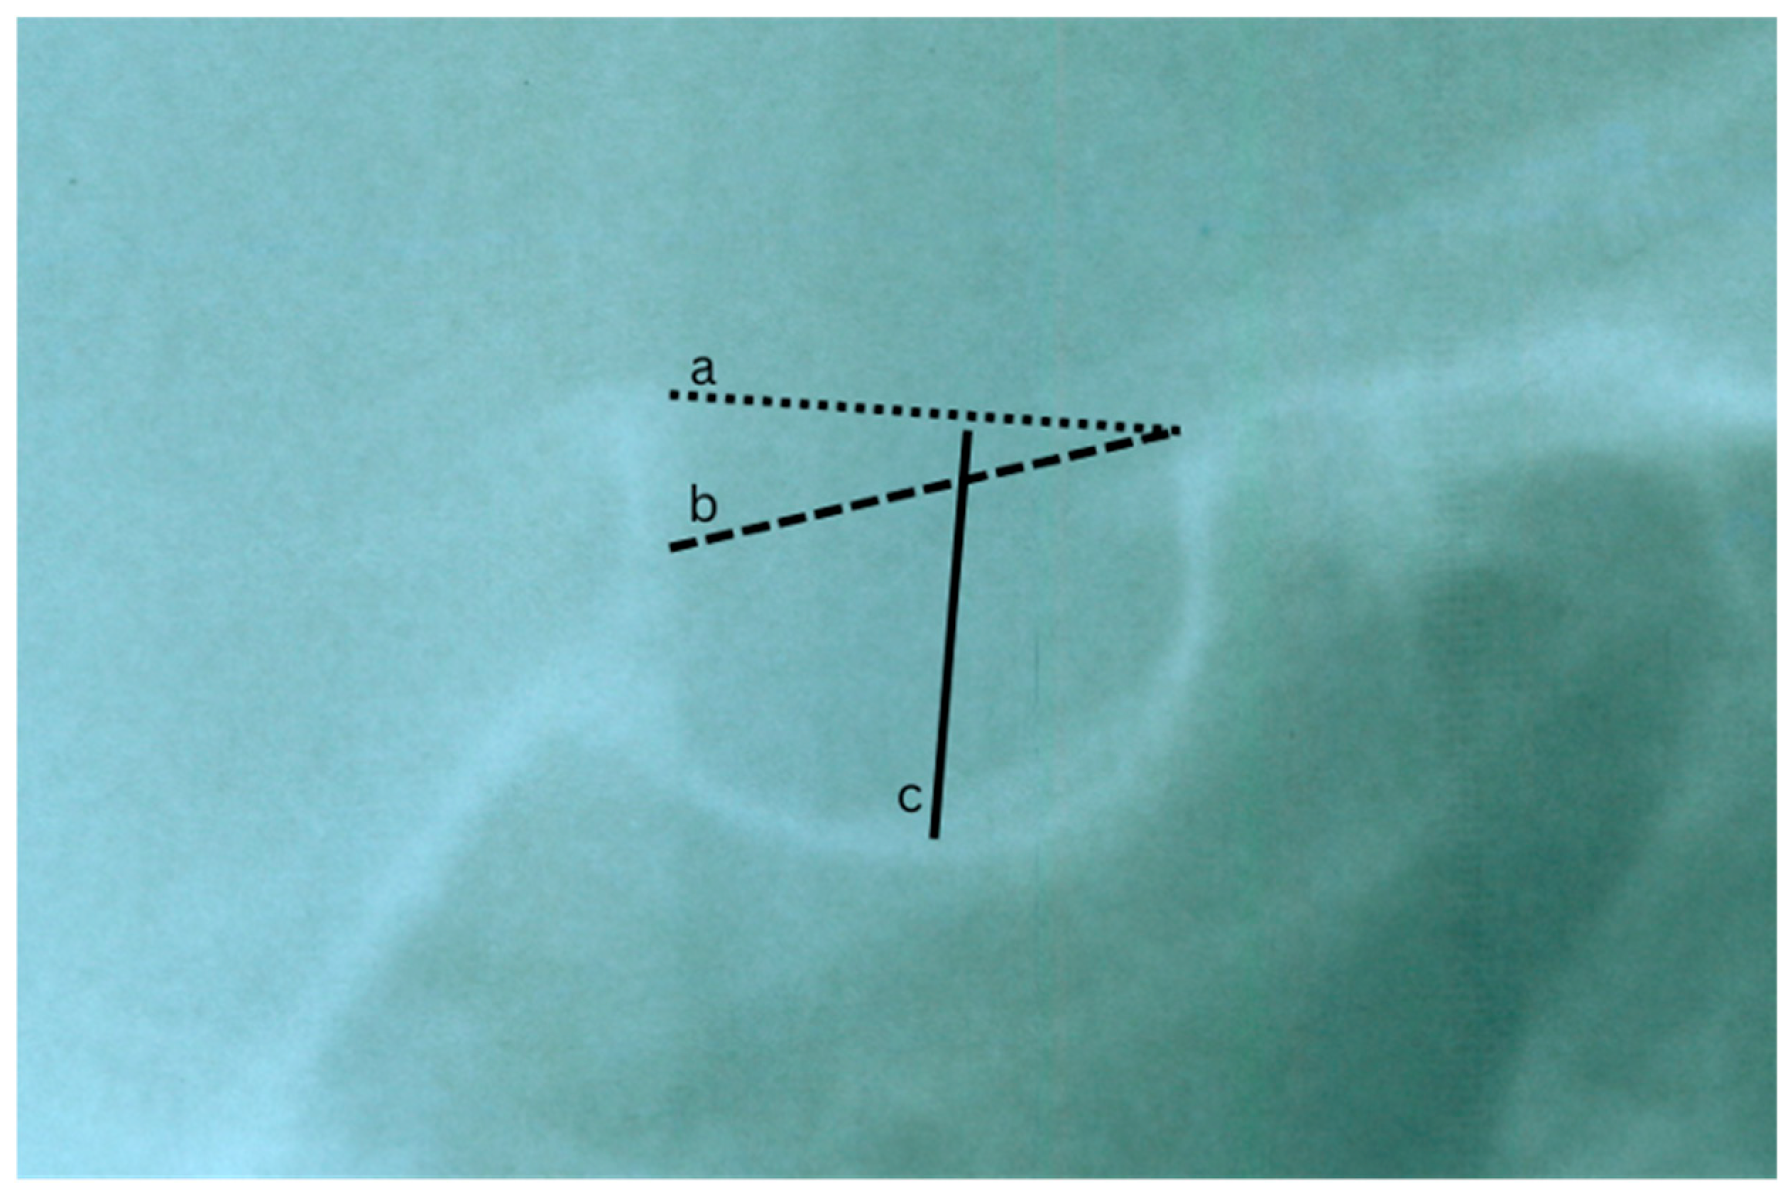

| Russell and Kjær 1999 Denmark [16] | Observational Lateral cephalograms | 78 DS; 4 months–50 years | Qualitative description | Author-defined (3 shape types) | Majority with near-normal morphology; few anterior/floor deviations | No control group; subjective classification |

| Korayem and AlKofide 2015 Saudi Arabia [18] | Observational Lateral cephalograms | 60 DS, 60 controls 12–22 years | Linear: length, depth, diameter | Standardized (Axelsson classification) | DS individuals showed increased depth and diameter and more shape deviations | Small sample; no longitudinal data |

| Hasan et al. 2019 Malaysia [19] | Observational CT scan | 50 DS, 50 controls; 0–35 years | Linear: heights (A/M/P), length, width, diameter, area | Modified standardized morphological criteria (U, J, shallow) | Several dimensions differed significantly; DS had U/J predominance | Sample limited to one population; generalizability limited |

| Aghimien 2022 Nigeria [21] | Cross-sectional descriptive Lateral cephalograms | 29 DS (size), 25 DS. 10–20 years | Linear: length, depth, diameter | Author-defined | Shorter length; pyramidal shape common; sex-related variation | Small sample; no control group; indirect norm comparison |

| Papaefthymiou et al. 2023 Turkey [20] | Retrospective Lateral cephalograms | 24 DS, 48 controls. 8–13 years | Linear: heights, length, width, area; geometric shape analysis | Standardized morphometric analysis (Procrustes + PCA) | DS group showed increased dimensions and distinct shape patterns | Small sample; no advanced imaging |